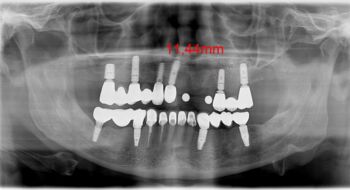

So sehen Implantate aus, die wie wor 20 Jahren gesetzt haben

Umso interessanter ist es dann, wenn man Röntgenbilder des nachbehandelenden Kollegen zu sehen bekommt, die einen Zustand aufzeigen, dass damals hier inserierte Implantate auch nach über 20 Jahren noch voll ossoeintegriert im Knochen stehen und prothetisch neu versorgt werden können, so man denn noch an verfügbare Ersatzteile kommt.

Gleiches gilt für den darauf sitzenden Zahnersatz. Achtung: Im Oberkiefer im Übergang zwischen Implantataufbau und Kronenversorgung ein sogenannter "burn-out" Röntgeneffekt. Will sagen: in der klinischen Inspektion zeigt sich kein nennennswerter Spalt, wie auf dem Röntgenbild.